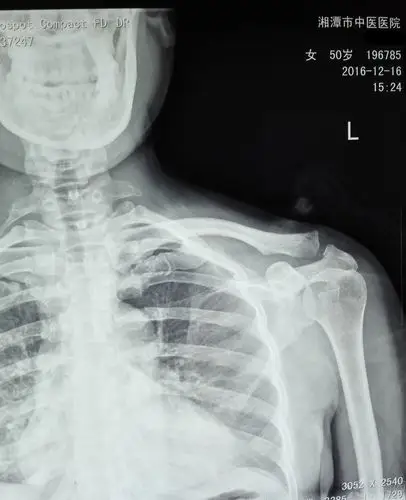

肩锁关节脱位关节镜微创复位固定

肩锁关节脱位

国际蒙医院骨伤科今日成功完成一例肩锁关节脱位肩关节镜喙锁韧带重建

武磊伤情曝光 肩锁关节脱位触目惊心

请问左肩锁关节脱位需要手术吗

肩锁关节脱位手术治疗及康复第一周

肩锁关节脱位的保守治疗 [病例帖]